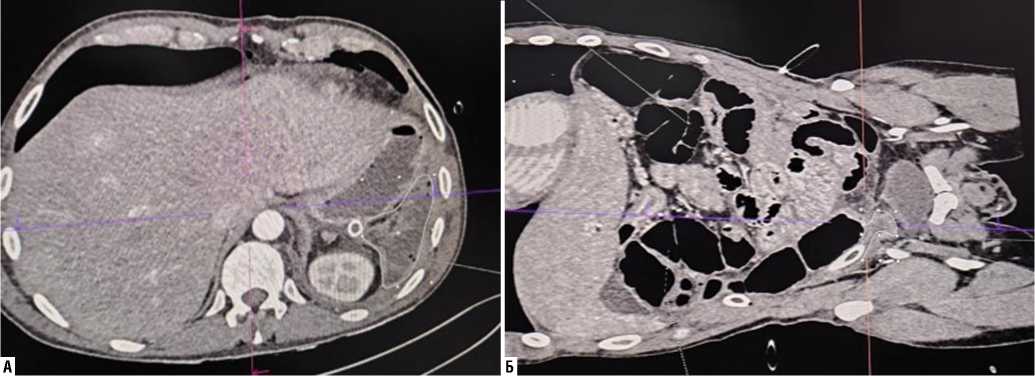

В диагностике перфоративных ОЯ тонкой кишки наиболее ценным неинвазивным методом следует признать компьютерную томографию с внутривенным контрастированием, выполняемую в ангиогенном и нативном режимах, которая достоверно у 92,8% раненых продемонстрировала ишемические зоны кишечника, наличие свободного газа и жидкости в брюшной полости, нарушение микроциркуляции сосудов брыжейки, наличие и локализацию дефекта кишечной стенки (Рис. 4). УЗИ оказалось малоинформативным при этой патологии.

Рис. 4. МСКТ брюшной полости с контрастированием при перфорации острой язвы тонкой кишки (наличие газа, свободной жидкости (А), дефекты стенки тонкой кишки (Б)).